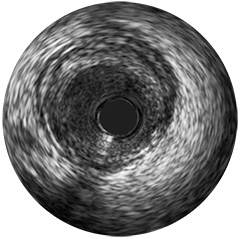

Figura 2